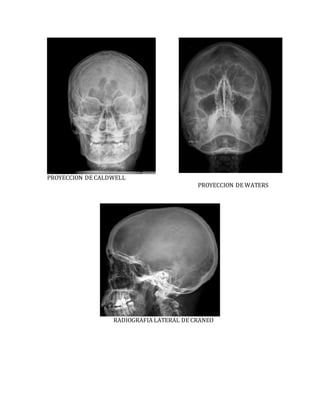

PROYECCION DE CALDWELL

PROYECCION DE WATERS

RADIOGRAFIA LATERAL DE CRANEO

PROYECCION DE CALDWELL PROYECCIONDE WATERS RADIOGRAFIA LATERAL DE CRANEO